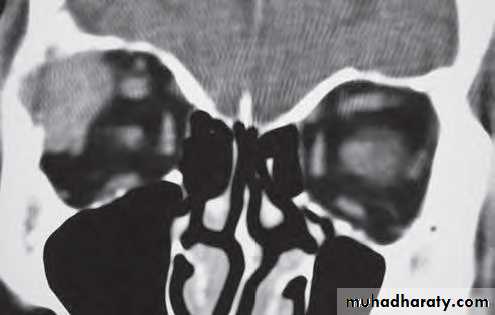

Investigation: CT shows a soft tissue mass with thinning or erosion of the bony walls of the sinus.

Treatment involves complete excision.